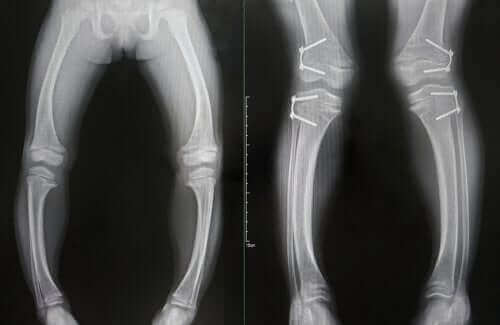

Riisitautidiagnoosi perustuu röntgenkuvaukseen ja laboratoriokokeissa todettaviin löydöksiin. Tietyt röntgenkuvamuutokset, madaltanut seerumin kalsium- ja fosfaattipitoisuus, suurentunut alkalisen fosfaatin aktiivisuus sekä vähentynyt kalsiumin eritys virtsaan viittaavat riisitautiin.